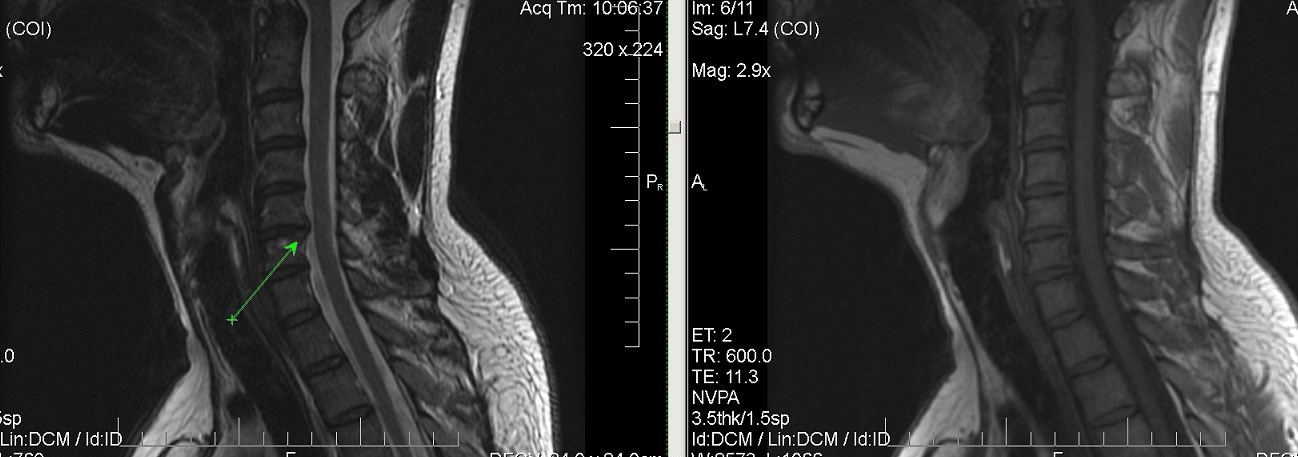

Мрт картина дегенеративно дистрофических изменений пояснично крестцового отдела позвоночника